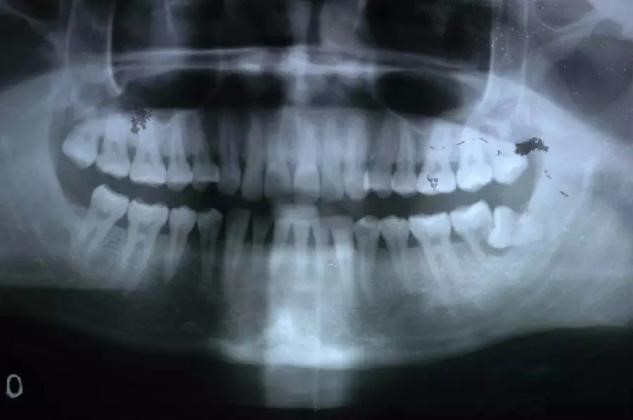

阻生齿是第三磨牙(即智齿)部分萌出或完全不能萌出,且以后也不会自行萌出的牙。这种萌出异常是由邻牙、骨或软组织的阻碍而引起的。很多人到了一定的年龄都会长出阻生齿,但是却不愿意拔出。有些阻生齿不会带来很大的影响,可以不拔出,但是有些不拔就会影响到其他的牙齿,造成一定的危害。那么,阻生齿不拔有什么危害呢?

2、磨牙龋齿:对于向前倾斜的阻生智齿,食物通常积聚在相邻牙齿之间,这容易导致相邻牙齿(下第二磨牙)的龋齿。这种龋齿不容易被发现,一旦出现疼痛(急性牙髓炎),牙冠通常会严重受损。出现龋齿、牙髓炎,甚至牙齿不能保留。第二磨牙缺失对咀嚼功能有很大影响,也很难用义齿修复。